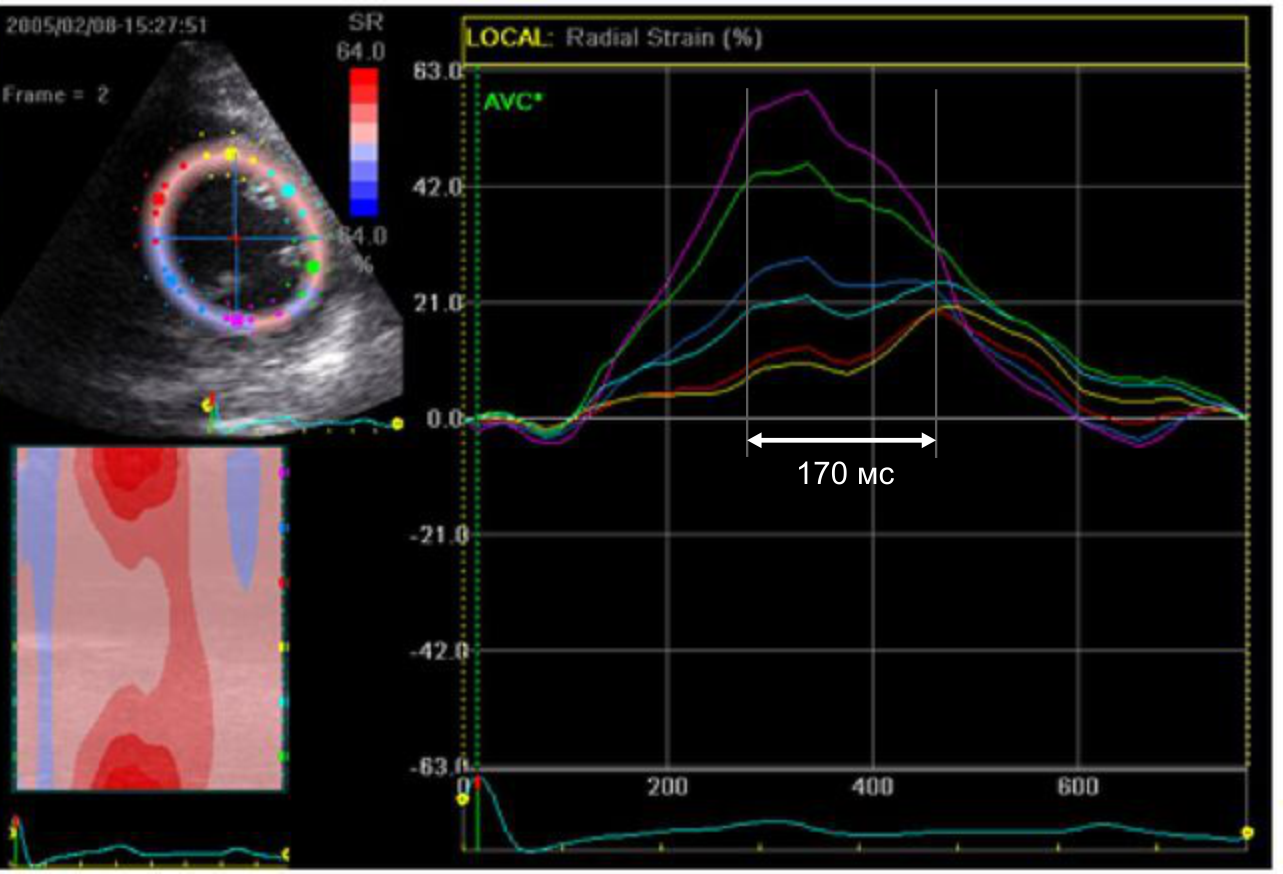

Эхокардиография является полезной методикой для стратификации риска и оценки прогноза после острого инфаркта миокарда. Показано, что для получения прогностической информации можно использовать множество традиционных эхокардиографических параметров, таких как объёмы и фракция выброса левого желудочка, индекс движения стенки, объём левого предсердия и наличие митральной регургитации. Разработка методов тканевой допплерографии и “speckle tracking” привела к появлению новых прогностических параметров, таких как деформация, скорость деформации и диссинхрония левого желудочка. Методика контрастной эхокардиографии позволяет оценивать перфузию миокарда и целостность микрососудистого кровоснабжения, предоставляет ценную информацию о жизнеспособности миокарда, тесно связанной с прогнозом. Стресс-эхокардиография позволяет выявить ишемию и жизнеспособный миокард, допплерография коронарных артерий — оценить резерв коронарного кровотока, и, наконец, трёхмерная эхокардиография даёт оптимальную информацию об объёмах, функции и сферичности левого желудочка, которые также являются важными параметрами долгосрочного прогноза.